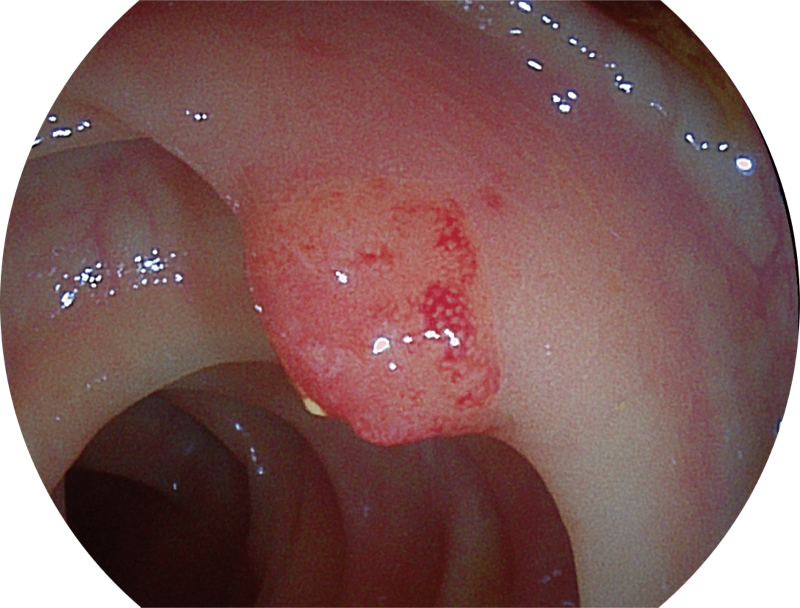

能够凸显黏膜浅层血管轮廓和黏膜表面微结构,适用于中、近景观察下的早癌精确诊断。

能够凸显黏膜浅层和中层血管轮廓,适用于中、远景观察下的病灶识别和早癌筛查。